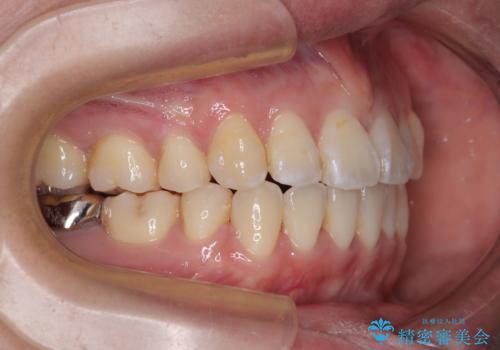

- 上下の出っ歯を気にして来院された患者様です。

口元を積極的に引っ込めるために、上下左右の第一小臼歯を4本抜歯することとしました。

また、上下前歯は舌の突出癖による開咬となっていたため、舌のトレーニングを徹底するよう指示しました。

舌突出癖の改善トレーニングは、仕上がり、治療期間、そして治療後の後戻りに大きな影響を及ぼします。

トレーニングをしっかりと行っていただいたため、スッキリとした口元に仕上がりました。